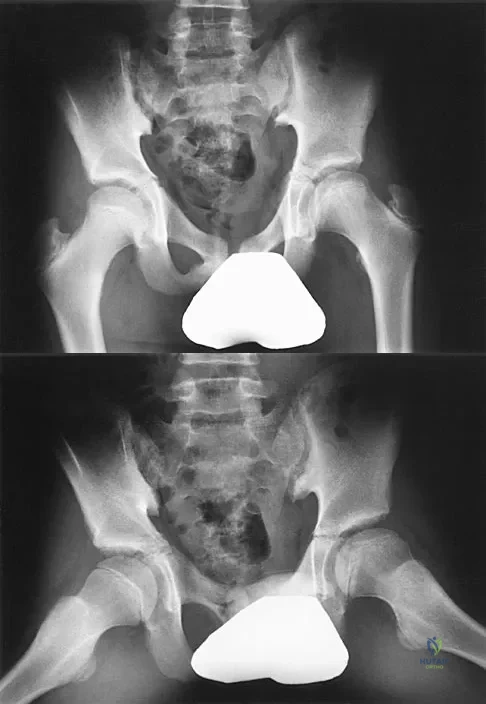

What is the most common long-term complication of the fracture shown in Figure 32?

The fracture pattern shown in the radiograph involves both a talar neck fracture and a talar body fracture. The body fracture propagates into the subtalar joint, with significant risk for the development of arthritis in that surface even with an anatomic reduction. In addition, Canale and Kelly reported a 25% incidence of malunion of talar neck fractures, with varus angulation occurring most frequently. Of these patients, 50% required a secondary surgical procedure because of the development of degenerative joint disease of the subtalar joint. Canale ST, Kelly FB Jr: Fractures of the neck of the talus: Long-term evaluation of seventy-one cases. J Bone Joint Surg Am 1978;60:143-156.